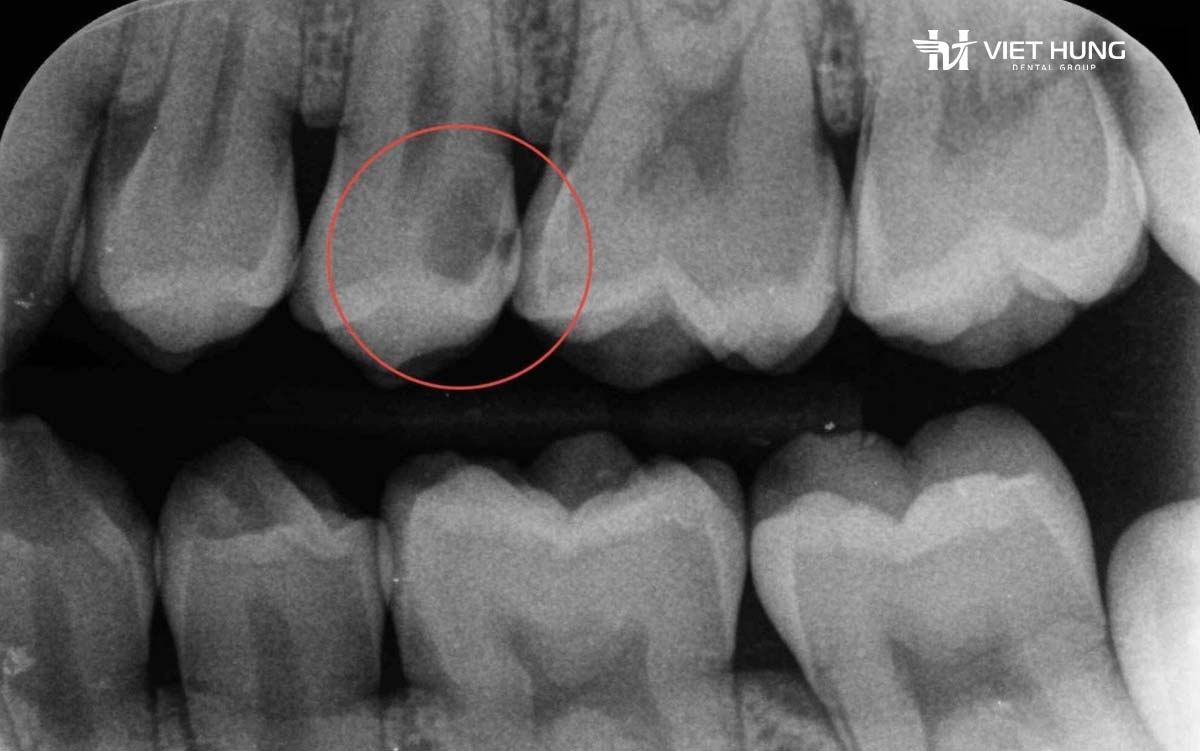

Ở giai đoạn đầu, sâu kẽ răng thường không gây đau và không tạo lỗ sâu rõ ràng. Người bệnh khó nhận biết nếu không có thăm khám nha khoa hoặc chụp X-quang cắn cánh. Khi xuất hiện triệu chứng rõ rệt, tổn thương thường đã lan sâu vào ngà răng hoặc tiến sát buồng tủy.

Sâu kẽ răng là tình trạng mô răng bị phá hủy tại vùng tiếp xúc giữa hai răng kế cận. Đây là khu vực rất khó làm sạch nếu chỉ chải răng thông thường, đồng thời cũng khó quan sát bằng mắt thường.

Sâu kẽ răng xuất hiện ở mặt bên của răng, nơi hai răng tiếp xúc với nhau. Mảng bám và thức ăn dễ tích tụ tại đây, đặc biệt ở những người có răng mọc khít, chen chúc hoặc phục hình – chỉnh nha nhưng vệ sinh chưa đúng cách.